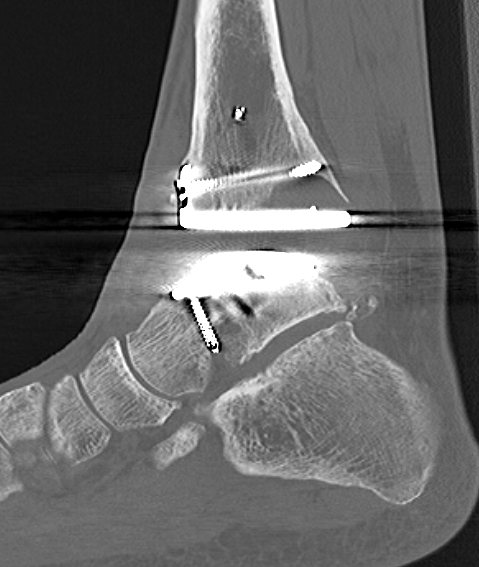

CT

Evaluate bone stock to determine if TAR is appropriate

Tibial cut

- distal alignment jig / extramedullar jig +/- image intensifier +/- patient specific jigs

- resect few mm above eroded bone

- preserve medial and lateral malleolus

Talar dome resurfacing

- jig to make chamfer cuts

Insert mobile / fixed bearing